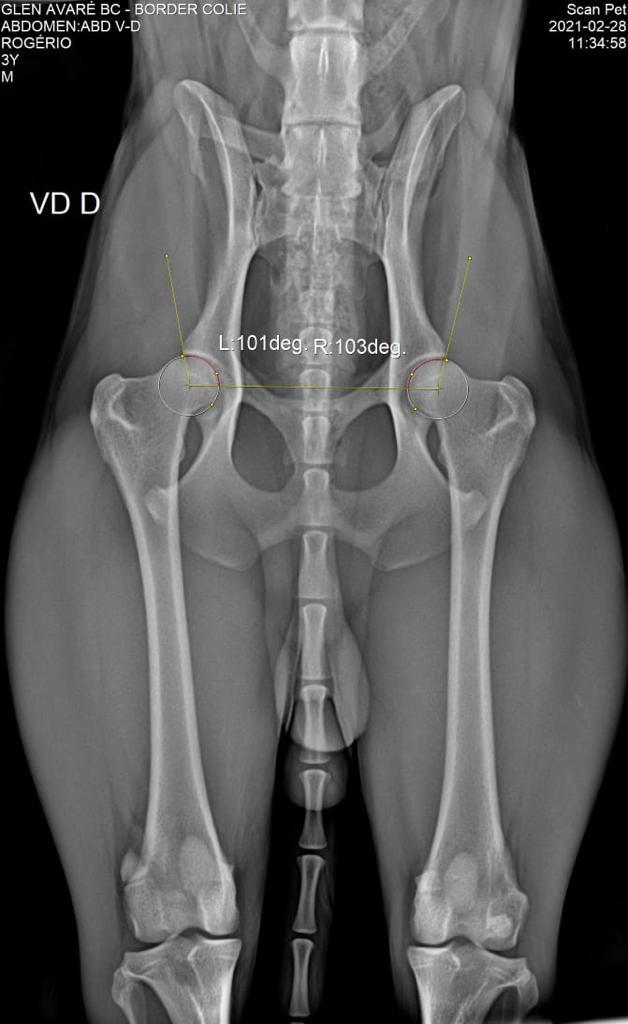

DISPLASIA

28/02/2021

ADEQUADO GRAU B

SCANPET

LAUDO

CHAPA